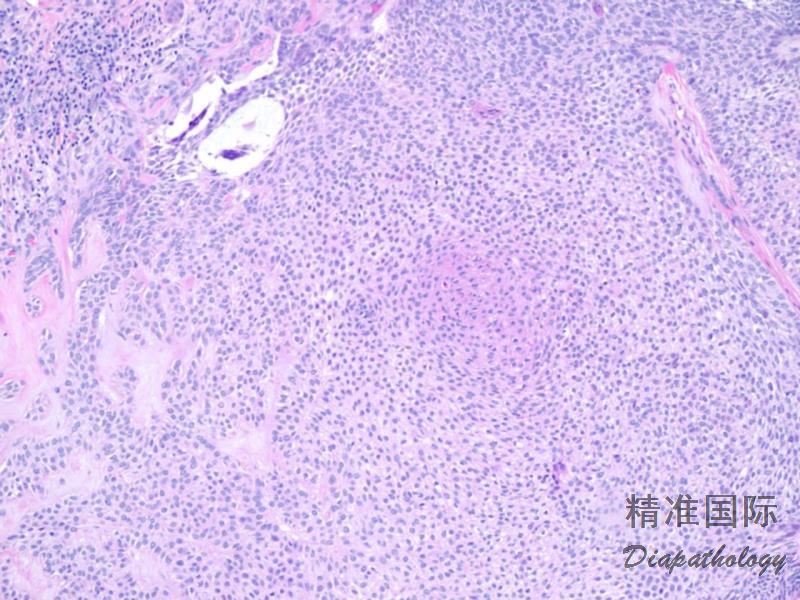

2. 肿瘤以出现细基底样上皮细胞索、角质囊肿和致密的纤维间质三联征为特征;

3. 基底样细胞小。核呈卵圆形,胞浆少,无明显异型性;

4. 角质囊肿多见,有的较大,常见钙化;

5. 间质有大量致密的胶原纤维。